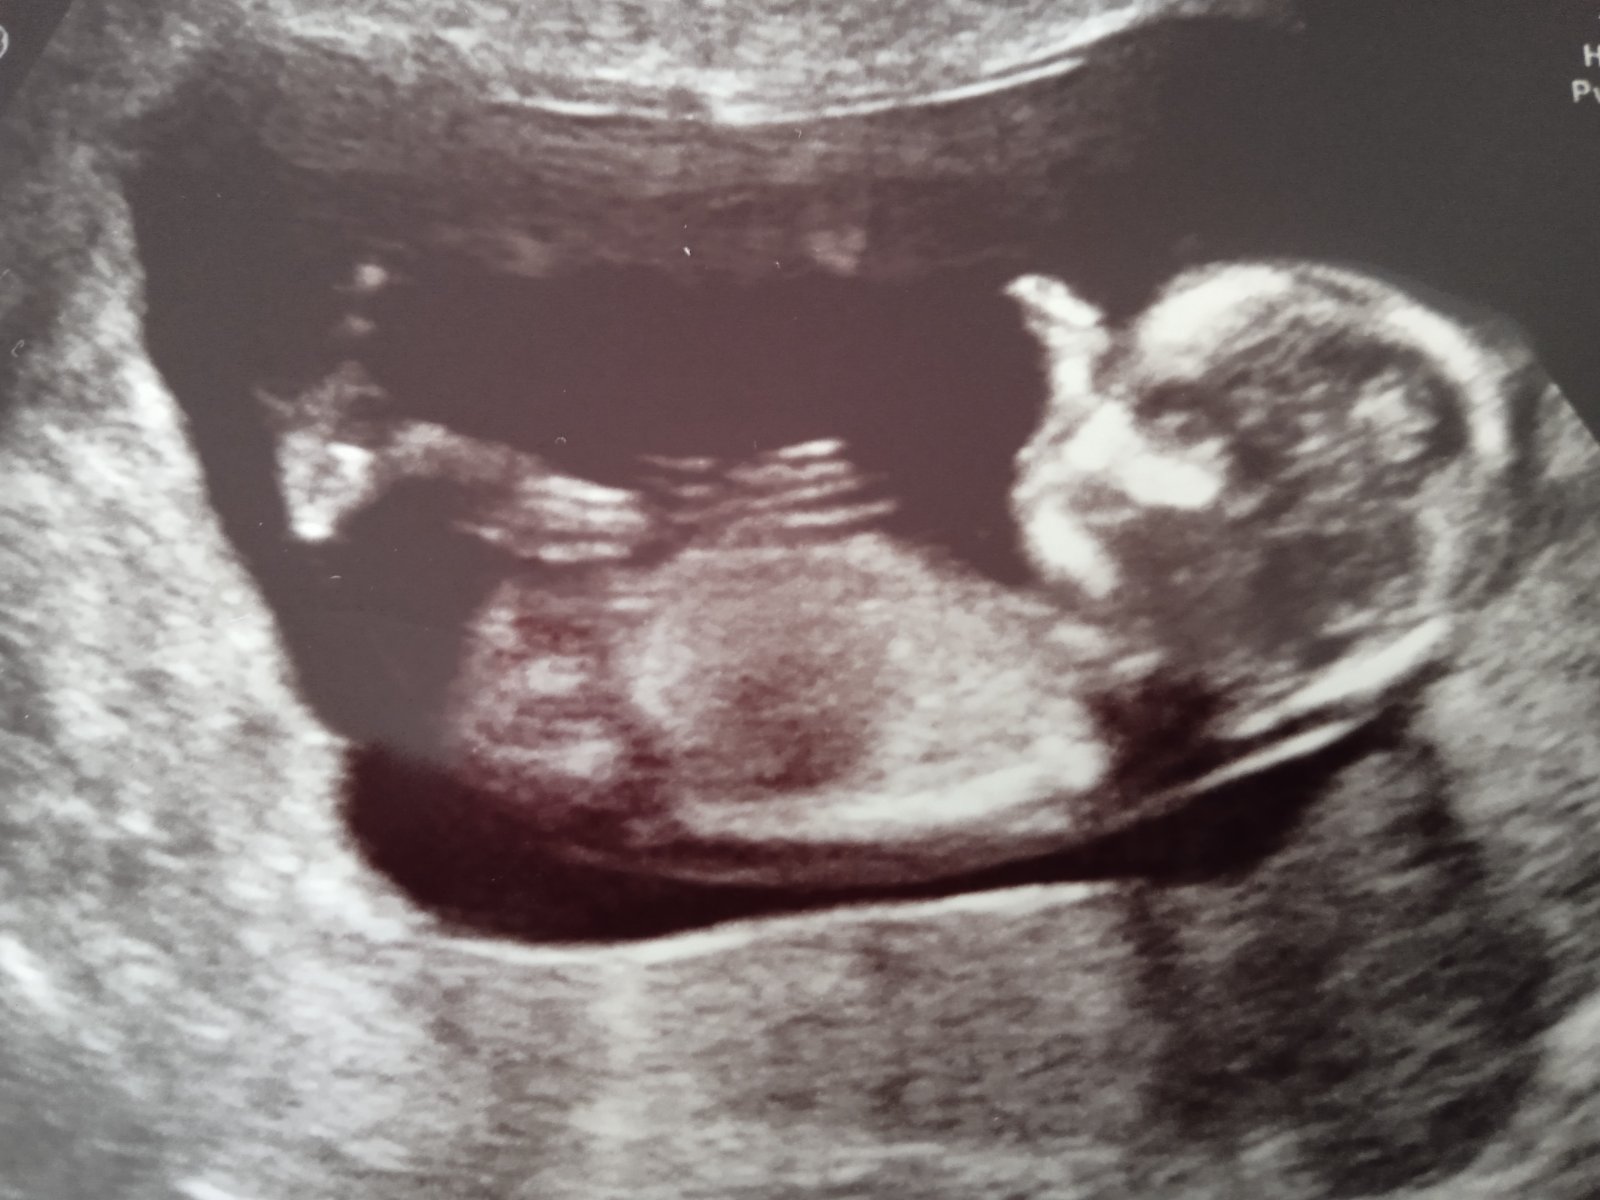

Screening ve 13. tt - foto. Našel by někdo pohlavní hrbolek?

já si myslím že tam není nic vidět, co doktor ten se k tomu nevyjádřil ?